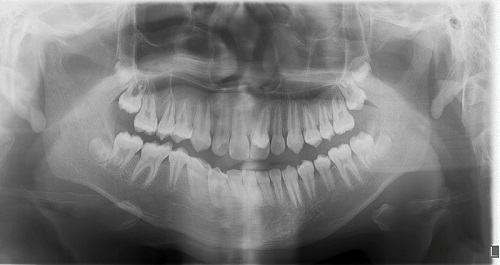

Paciente varón de 6 años, sin antecedentes familiares ni personales de interés, que acude a la consulta de Pediatría para la revisión de 6 años, donde se observan múltiples caries y se deriva a la consulta de Odontología. En la exploración intraoral presentaba los incisivos centrales superiores parcialmente erupcionados con el 21 rotado, diastema interincisivo y ausencia de 62 y sin espacio para la erupción de 22 (Fig. 1). En la línea media por palatino se aprecia la erupción parcial de diente conoide con la presunción de diente supernumerario mesiodens que no presenta movilidad; en oclusión se aprecia mordida cruzada de dicho supernumerario que mantiene incisivos inferiores vestibulizados (clase I molar). Se solicitó una ortopantomografía para valorar la posición y el estado de la erupción de los incisivos superiores, así como descartar presencia de otros supernumerarios o agenesias. La radiografía mostraba la presencia de un diente supernumerario mesiodens en la línea media (Fig. 2). Se hallaba en posición vertical y presentaba una forma conoide. Provocaba un gran diastema interincisal e impedía la correcta erupción de los incisivos centrales y laterales superiores, incluso alterando la oclusión y correcta posición de incisivos inferiores. Se informó a la madre de la necesidad de realizar la extracción para la correcta erupción dentaria del sector anterior y, dada la colaboración del paciente, se realiza en la consulta con anestesia tópica y posteriormente infiltrativa, procediendo a la extracción del mismo (Fig. 3). En la extracción se observa lesión periapical compatible con quiste folicular que se envía al Servicio de Anatomía Patológica para su estudio. El paciente precisará controles periódicos para controlar la erupción dentaria y valorar la necesidad de un tratamiento ortodóncico posterior para cerrar el diastema interincisal y permitir, además, la erupción de los incisivos laterales superiores.

| Figura 1. Paciente con mesiodens en línea media interincisiva, posición vertical, que produce la rotación del 21 impidiendo su correcta erupción |